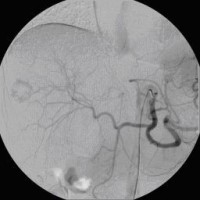

« Zurück Superselektive transarterielle Chemoembolisation (TACE) mit Sondierung eines tumorversorgenden Gefäßes 1 (Bild 3 von 5) Vorwärts »